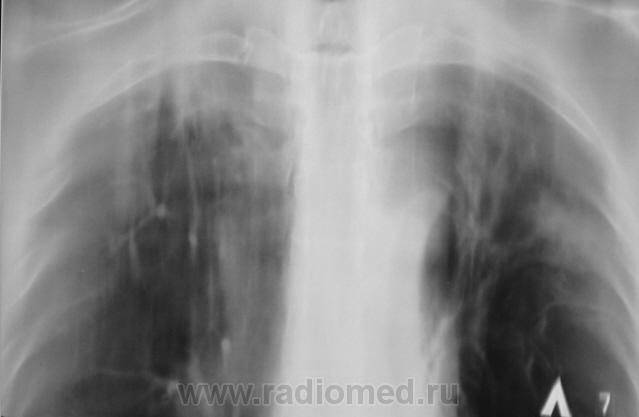

Болел, давно снят с учета. Клиническое излечение. Рецидив?

Рентгенограмма.